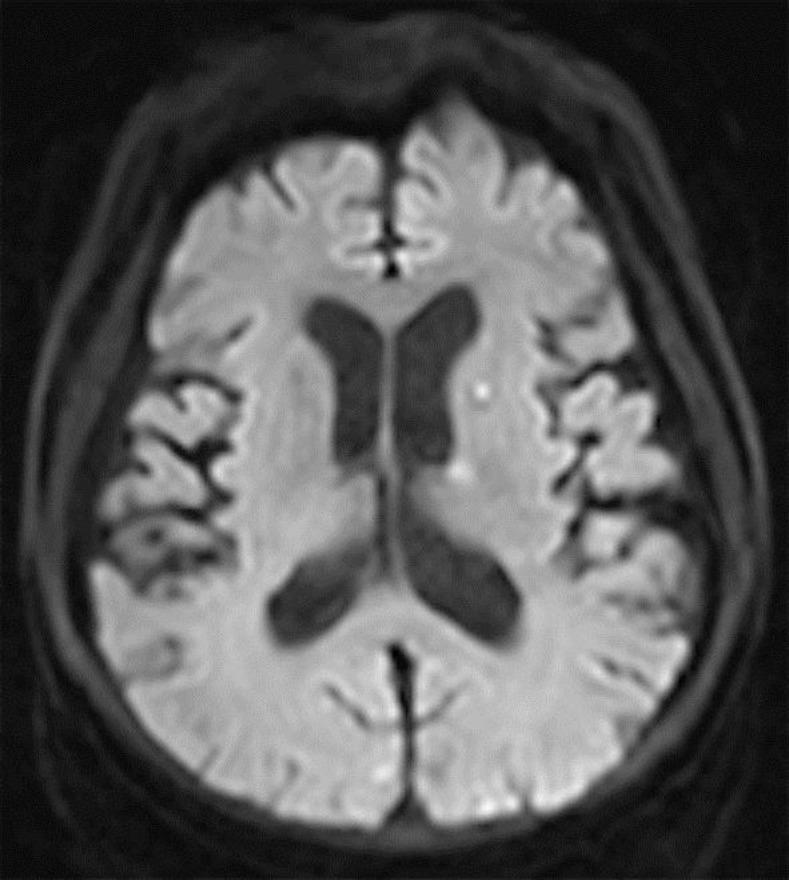

Guillain-Barré syndrome (GBS) is defined as an acute, autoimmune polyradiculoneuropathy. It is a rare disease that occurs at a rate of 1.11 cases per 100,000 person-years. However, once infected, up to 20%percnt; of patients develop severe disability, and approximately 5%percnt; die. There have been reports of GBS in different cancers. Among them, there are 6 previous reports of GBS in small cell lung cancer. Here, we report a case of a 52-year-old man who was diagnosed with GBS in the setting of small cell lung cancer with chemotherapy.

吉兰-巴雷综合征(GBS)被定义为一种急性自身免疫性多发性神经根神经病。它是一种罕见疾病,发病率为每10万人年1.11例。然而,一旦感染,高达20%的患者会出现严重残疾,约5%的患者会死亡。已有不同癌症中GBS的报道。其中,既往有6例小细胞肺癌患者发生GBS的报道。在此,我们报告一例52岁男性患者,其在接受小细胞肺癌化疗时被诊断为GBS。